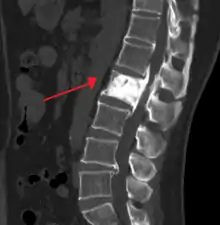

Initially, there is a marked increase in the rate of bone resorption in localized areas, caused by large and numerous osteoclasts. These localized areas of pathological destruction of bone tissue (osteolysis) are seen radiologically as an advancing lytic wedge in long bones or the skull. When this occurs in the skull, it is called osteoporosis circumscripta. The osteolysis is followed by a compensatory increase in bone formation induced by the bone-forming cells, called osteoblasts, that are recruited to the area. This is associated with accelerated deposition of lamellar bone in a disorganized fashion. This intense cellular activity produces a chaotic picture of trabecular bone ("mosaic" pattern), rather than the normal linear lamellar pattern. The resorbed bone is replaced and the marrow spaces are filled by an excess of fibrous connective tissue with a marked increase in blood vessels, causing the bone to become hypervascular. The bone hypercellularity may then diminish, leaving a dense "pagetic bone," also known as burned-out Paget's disease. A later phase of the disease is characterized by the replacement of normal bone marrow with highly vascular fibrous tissue.[24]